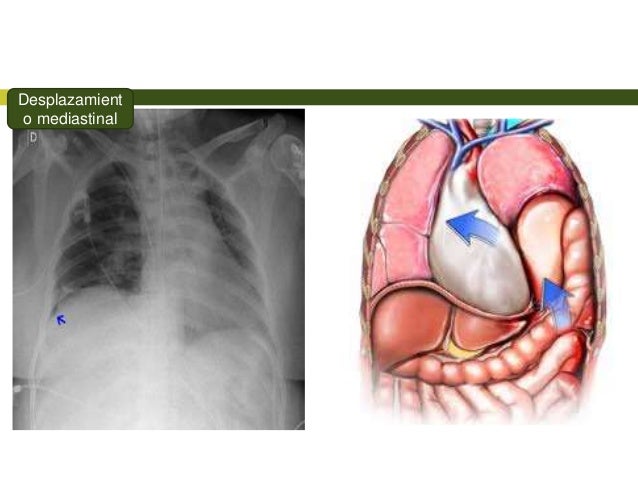

A Tensión.

El aire presente en el espacio pleural genera un incremento gradual de la presión intratorácica lo que lleva a una

desviación del mediastino y da como resultado un menor retorno venoso comprometiendo la función circulatoria.